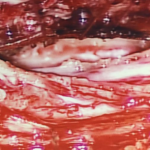

頸椎6/7節椎管位置長了一個1.6cm腫瘤嚴重地壓著脊髓

頸椎6/7節椎管位置長了一個1.6cm腫瘤嚴重地壓著脊髓

腫瘤嚴重地壓著脊髓

割除椎管腫瘤